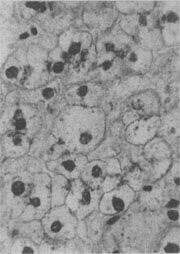

肝细胞气球样变

图1-17 肝细胞气球样变

病毒性肝炎时,肝细胞明显肿胀,胞浆疏松呈气球样

形态学:水肿的细胞体积增大,胞浆基质内水分含量增多,变得较为透明、淡染,胞核也常常被波及而增大、染色变淡、从而使整个细胞膨大如气球,故有气球变之称(图1-17)。电镜下,除可见胞浆基质疏松变淡外,尚可见线粒体肿胀及嵴变短、变少甚至消失;内质网则广泛解体、离断和发生空泡变。严重的水变性有时与渐进性坏死和坏死难以区分。